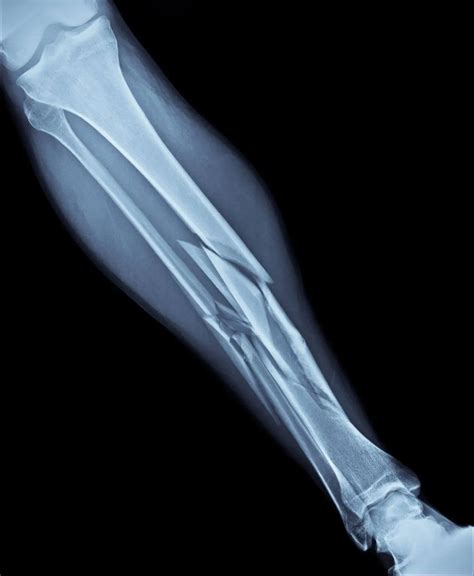

Fractures can be classified into several types based on their characteristics and the severity of the injury. Understanding these types can help in recognizing the appropriate treatment and recovery process.

Open vs. Closed Fractures

One of the key distinctions in fractures is whether the bone breaks through the skin or not.

• Open Fracture: Also known as a compound fracture, this type occurs when the broken bone penetrates the skin, creating an open wound. Open fractures are more susceptible to infection and require immediate medical attention.

• Closed Fracture: In this type, the bone breaks but does not penetrate the skin. Closed fractures are less likely to become infected but still require proper medical care.

Complete vs. Incomplete Fractures

Another important classification is based on whether the bone is completely or partially broken.

• Complete Fracture: The bone is broken into two or more pieces. This type often requires surgical intervention to realign the bone fragments.

• Incomplete Fracture: The bone is partially broken but still in one piece. This type is more common in children, whose bones are still growing and more flexible.

Displaced vs. Non-Displaced Fractures

Fractures can also be categorized based on the alignment of the bone fragments.

• Displaced Fracture: The bone fragments are not aligned properly and may overlap or be separated. This type often requires surgical intervention to realign the bone.

• Non-Displaced Fracture: The bone fragments remain aligned. This type is generally easier to treat and may only require immobilization with a cast or splint.

Comminuted Fractures

A comminuted fracture occurs when the bone shatters into three or more pieces. This type of fracture is often the result of high-impact trauma and can be challenging to treat. Surgical intervention is usually required to realign the bone fragments and stabilize the area.

Diagnosing Fractures

Diagnosing a fracture typically involves a combination of physical examination and imaging tests. The healthcare provider will assess the injury, looking for signs such as swelling, deformity, and tenderness. Imaging tests, such as X-rays, CT scans, or MRIs, are used to confirm the diagnosis and determine the type and severity of the fracture.